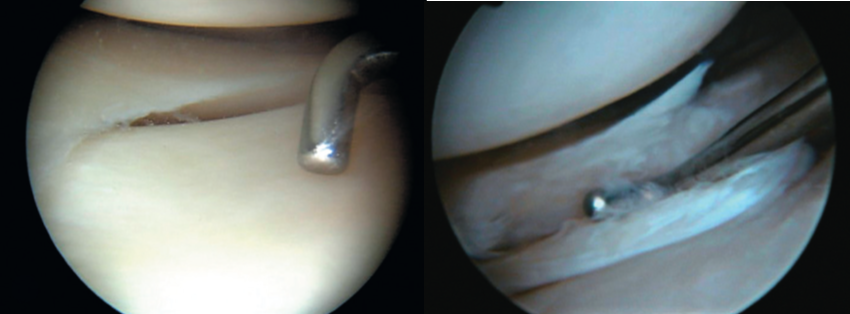

Los Meniscos

Son fibrocartílagos en forma de medialuna y tienen como funciones: Estabilizar la articulación de la rodilla, amortiguar, absorber carga y con esto protegen de daños a los cartílagos, nutren y lubrican además de estar implicados en la propiocepción de la rodilla.

Son avasculares en sus 2/3 partes lo que hace difícil su cicatrización espontánea y nos vemos en la necesidad de salvar al menisco haciendo un diagnóstico temprano y tratamiento artroscópico adecuado.